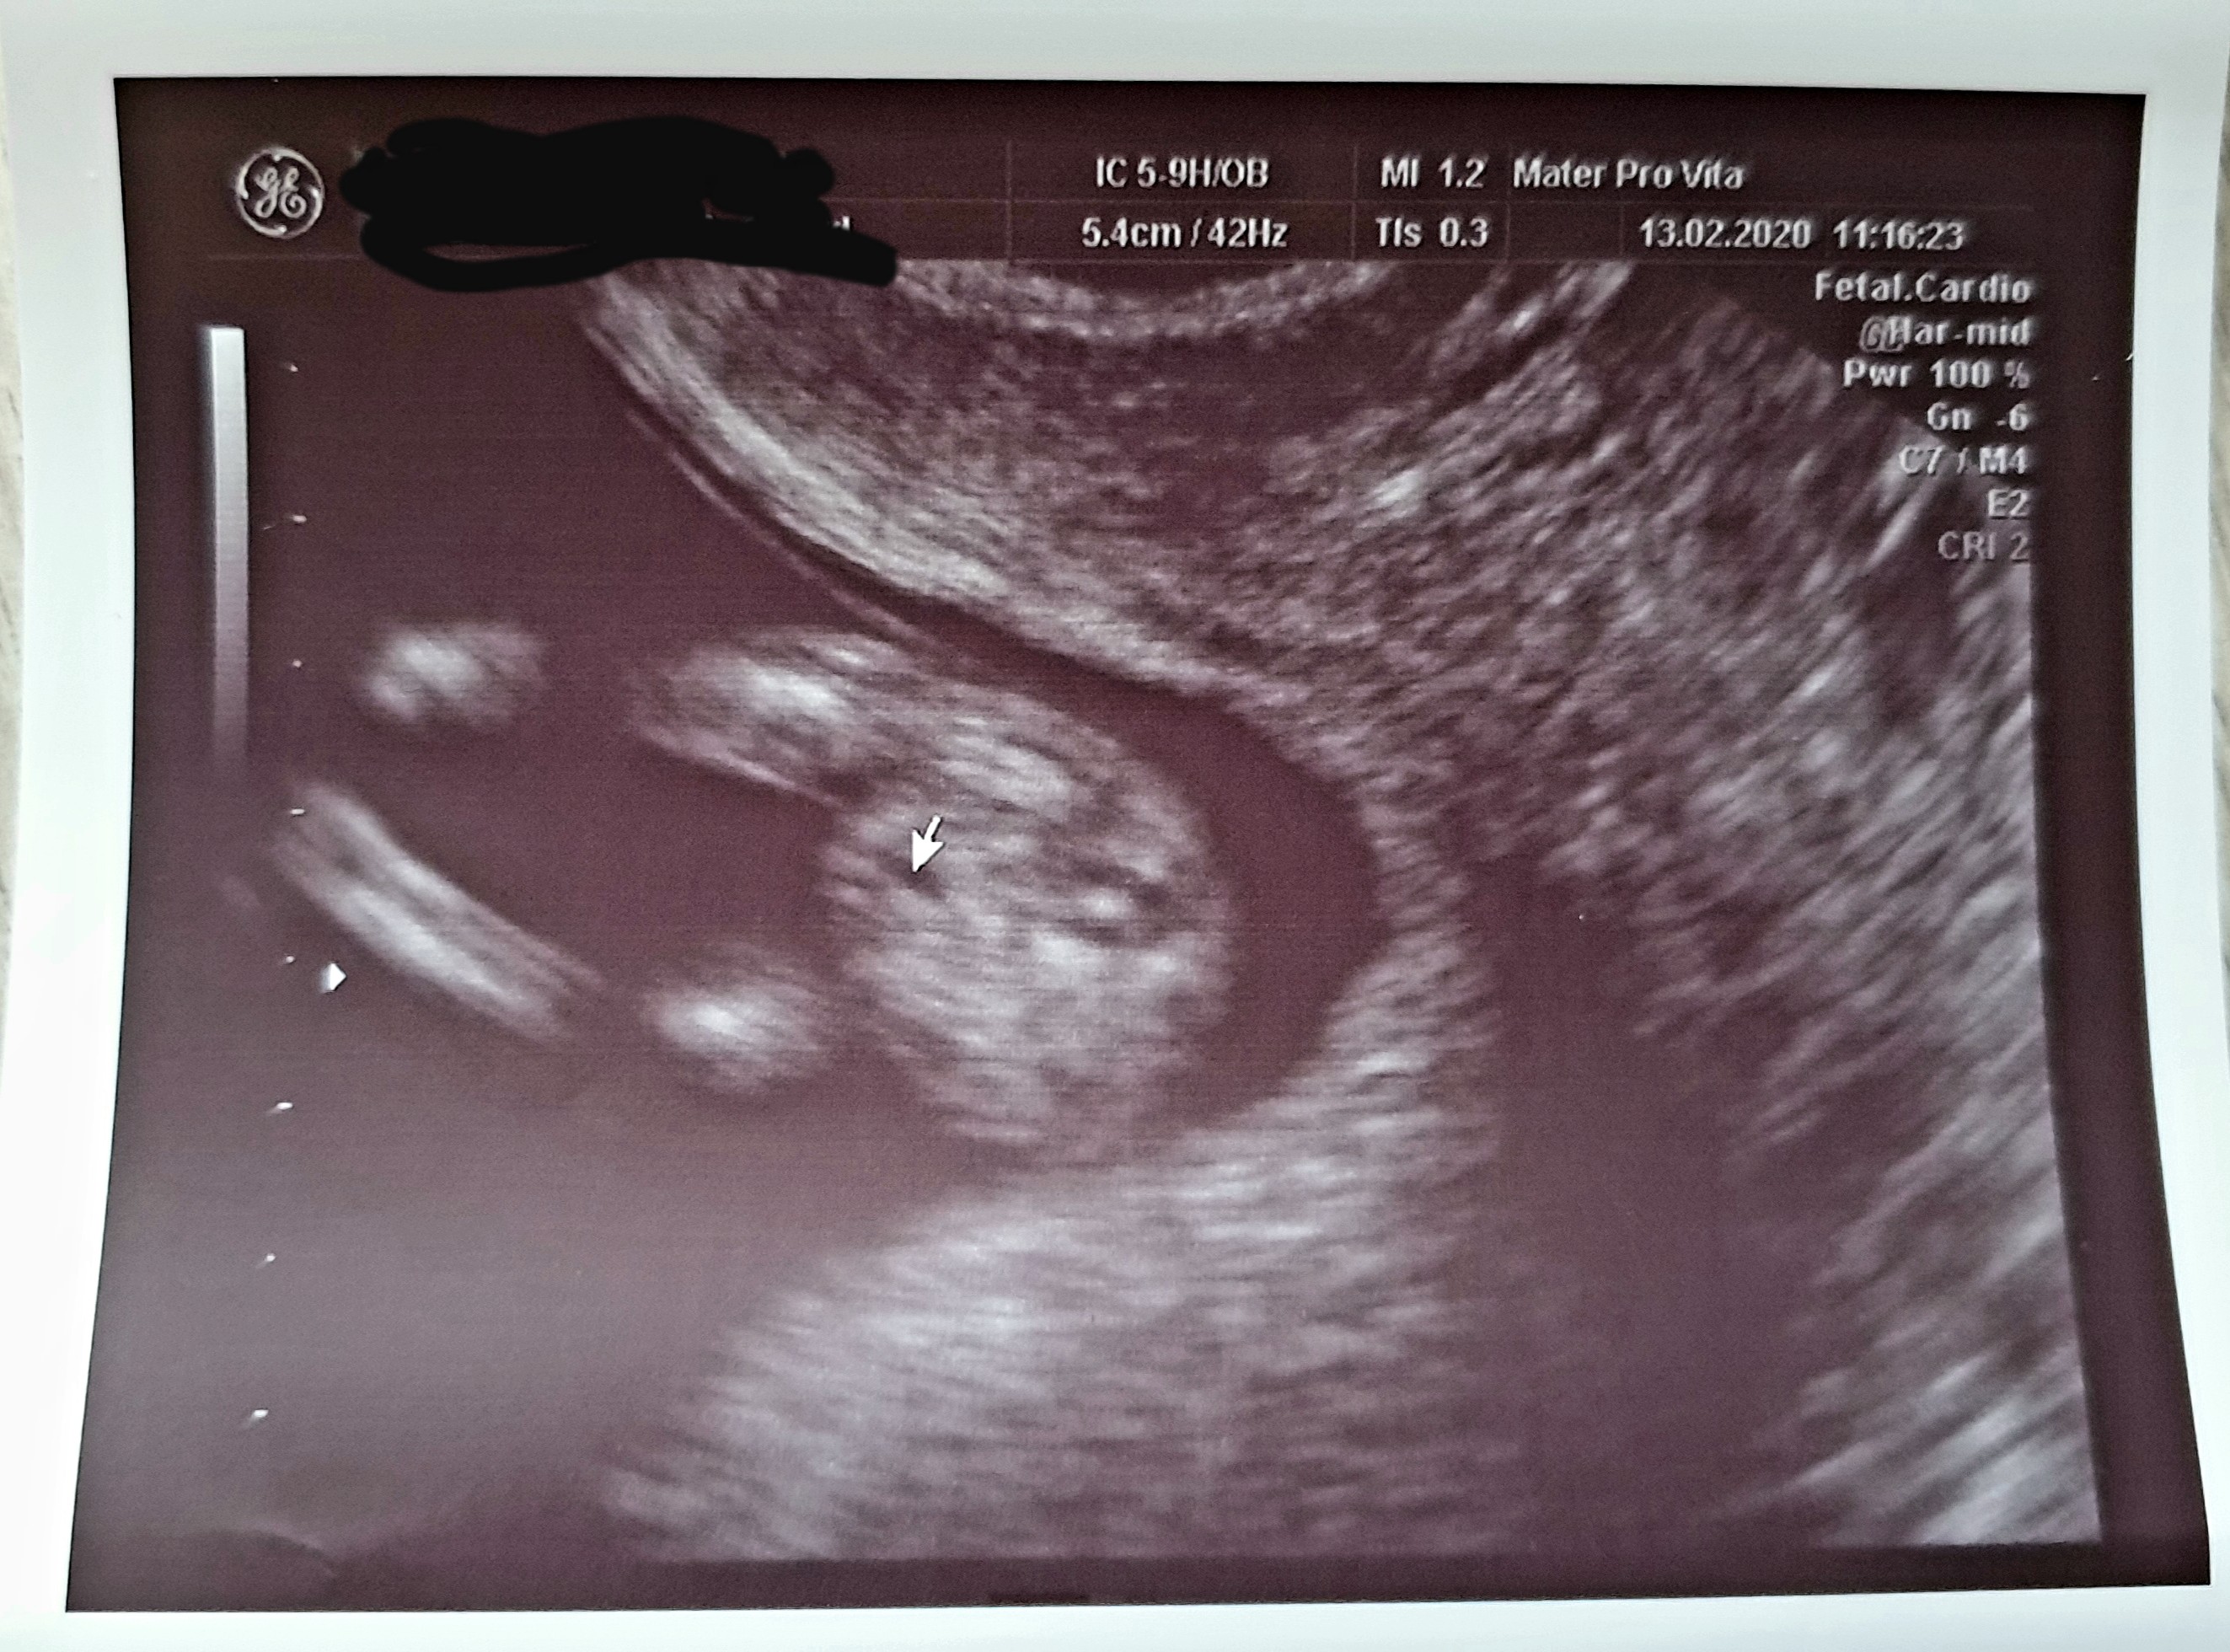

A ja mam takie zdjęcie z badań prenatalnych. Na moje oko siusiaka brak. Lekarka powiedziała że nie ocenia płci bo to że nie ma siusiaka nie znaczy że go nie będzie ( nie chciała nic sugerowac). 4 dni później byłam u mojej ginekolog, która ma dużo gorszy sprzęt i stwierdziła że coś tam widzi między nogami ale ręki sobie nie utnie. Jak wasze doswiadczenia? Co myslicie o tym zdjeciu? To zaznaczone to podobno uklad moczowy czy jakos tak.To jest 12 tydz i 5 dni. Oczywiście wiem że nie jesteście lekarzami ale może któraś z Was miała podobne zdjęcie bo ja w poprzedniej ciąży miałam identyczne ale wtedy czarno na białym było widać siusiaka.

A ja mam takie zdjęcie z badań prenatalnych. Na moje oko siusiaka brak. Lekarka powiedziała że nie ocenia płci bo to że nie ma siusiaka nie znaczy że go nie będzie ( nie chciała nic sugerowac). 4 dni później byłam u mojej ginekolog, która ma dużo gorszy sprzęt i stwierdziła że coś tam widzi między nogami ale ręki sobie nie utnie. Jak wasze doswiadczenia? Co myslicie o tym zdjeciu? To zaznaczone to podobno uklad moczowy czy jakos tak.To jest 12 tydz i 5 dni. Oczywiście wiem że nie jesteście lekarzami ale może któraś z Was miała podobne zdjęcie bo ja w poprzedniej ciąży miałam identyczne ale wtedy czarno na białym było widać siusiaka.Zobacz załącznik 1081843